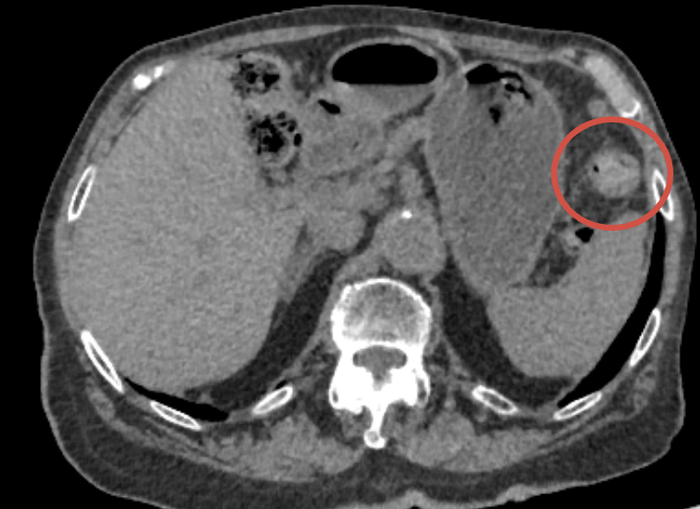

Что у меня — РМЖ, 2ст, опухоль располагается там, откуда начинает расти титечка, недалеко от подмышки, размер 1.2*1.5 до химозы, но была круглым шариком, после размеры по +0.2, но она плоская и по узи распалась на неоднородную структуру, был метастаз в подмышечный лимфоузел. Локация прям под кожей и невооруженным взглядом ее было видно. Изначально это была доброкачественная опухоль, типа фиброаденомы (узи от апреля), в начале лета я словила охуенную аллергию на два месяца и, как я думаю, она то и сыграла роль в этой неприятной истории. В июне я пошла на повторное узи, где меня почти похоронили загробным голосом (пост есть ниже), ну и пошла поехала вся круговерть с диагнозом, биопсией и проч.